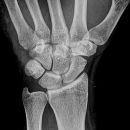

Handgelenk seitlich

Beurteilungskriterien

- Neigung der distalen Radiusgelenkfläche in der Sagittalebene: 10 – 15°

- Kontinuierliche Verlängerungsachse durch Radius, Lunatum, Capitatum und Os metacarpale III. Kontinuität von Handrücken und Unterarmrückfläche (Luxation, nicht-exakte Einstellung? -> Proc.styloideus ulnae im hinteren Radiusdrittel?)

- Scapholunärer Winkel 30 – 60°

- Verstreichen und Ventralverlagerung der volaren Fettstreifen vor dem M.flexor digitorum profundus und M.pronator quadratus

- Grundsätzlich gilt: unklare Verhältnisse -> CT-Indikation

Beispiele

Smith-Fraktur (2) volare Fragmentabkippung

Colles- Fraktur (2) dorsale Fragmentabkippung

Chauffeur-Fraktur (2) radialer Keilbruch

Barton-Fraktur (2) intraartikulär, dorsales Kantenfragment

Reversed Barton-Fraktur (2) intraartikulär, volares Kantenfragment